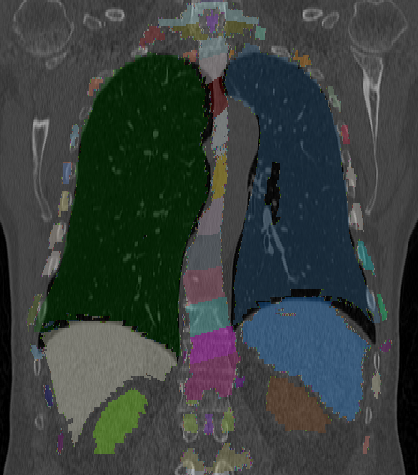

Figure 3: The result of multi-organ segmentation of a CT dataset (left), an example of the liver segmentation of a flat-panel CT scan of a liver (middle) and the warped visible human phantom overlay with a CT (right).